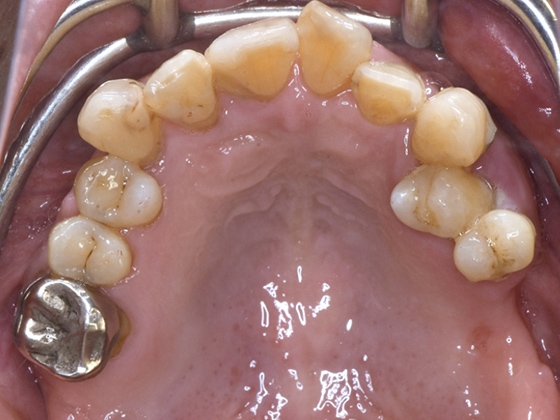

治療前

この症例では下顎の歯周病が特に進行していて、歯がクラグラで噛みにくい為、下の歯を抜歯してオールオン4で治療、上は特に歯周病が進行している左側の大臼歯を抜歯して経過観察することにしました。